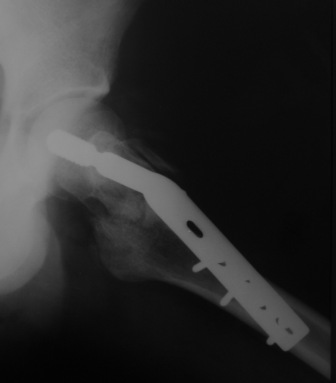

При межвертельных переломах с цефаломедуллярными гвоздями бывает, что проксимальый винт проходит или черед периферический отломок, или прямо над ним. И если остался диастаз, то этот винт при осевой нагрузке не дает сблизиться отломкам. Пример такого остеосинтеза в застарелом случае в приложении.

В качестве предупреждающей меры можно долотом разрушить латеральную стенку дистального отломка под винтом.